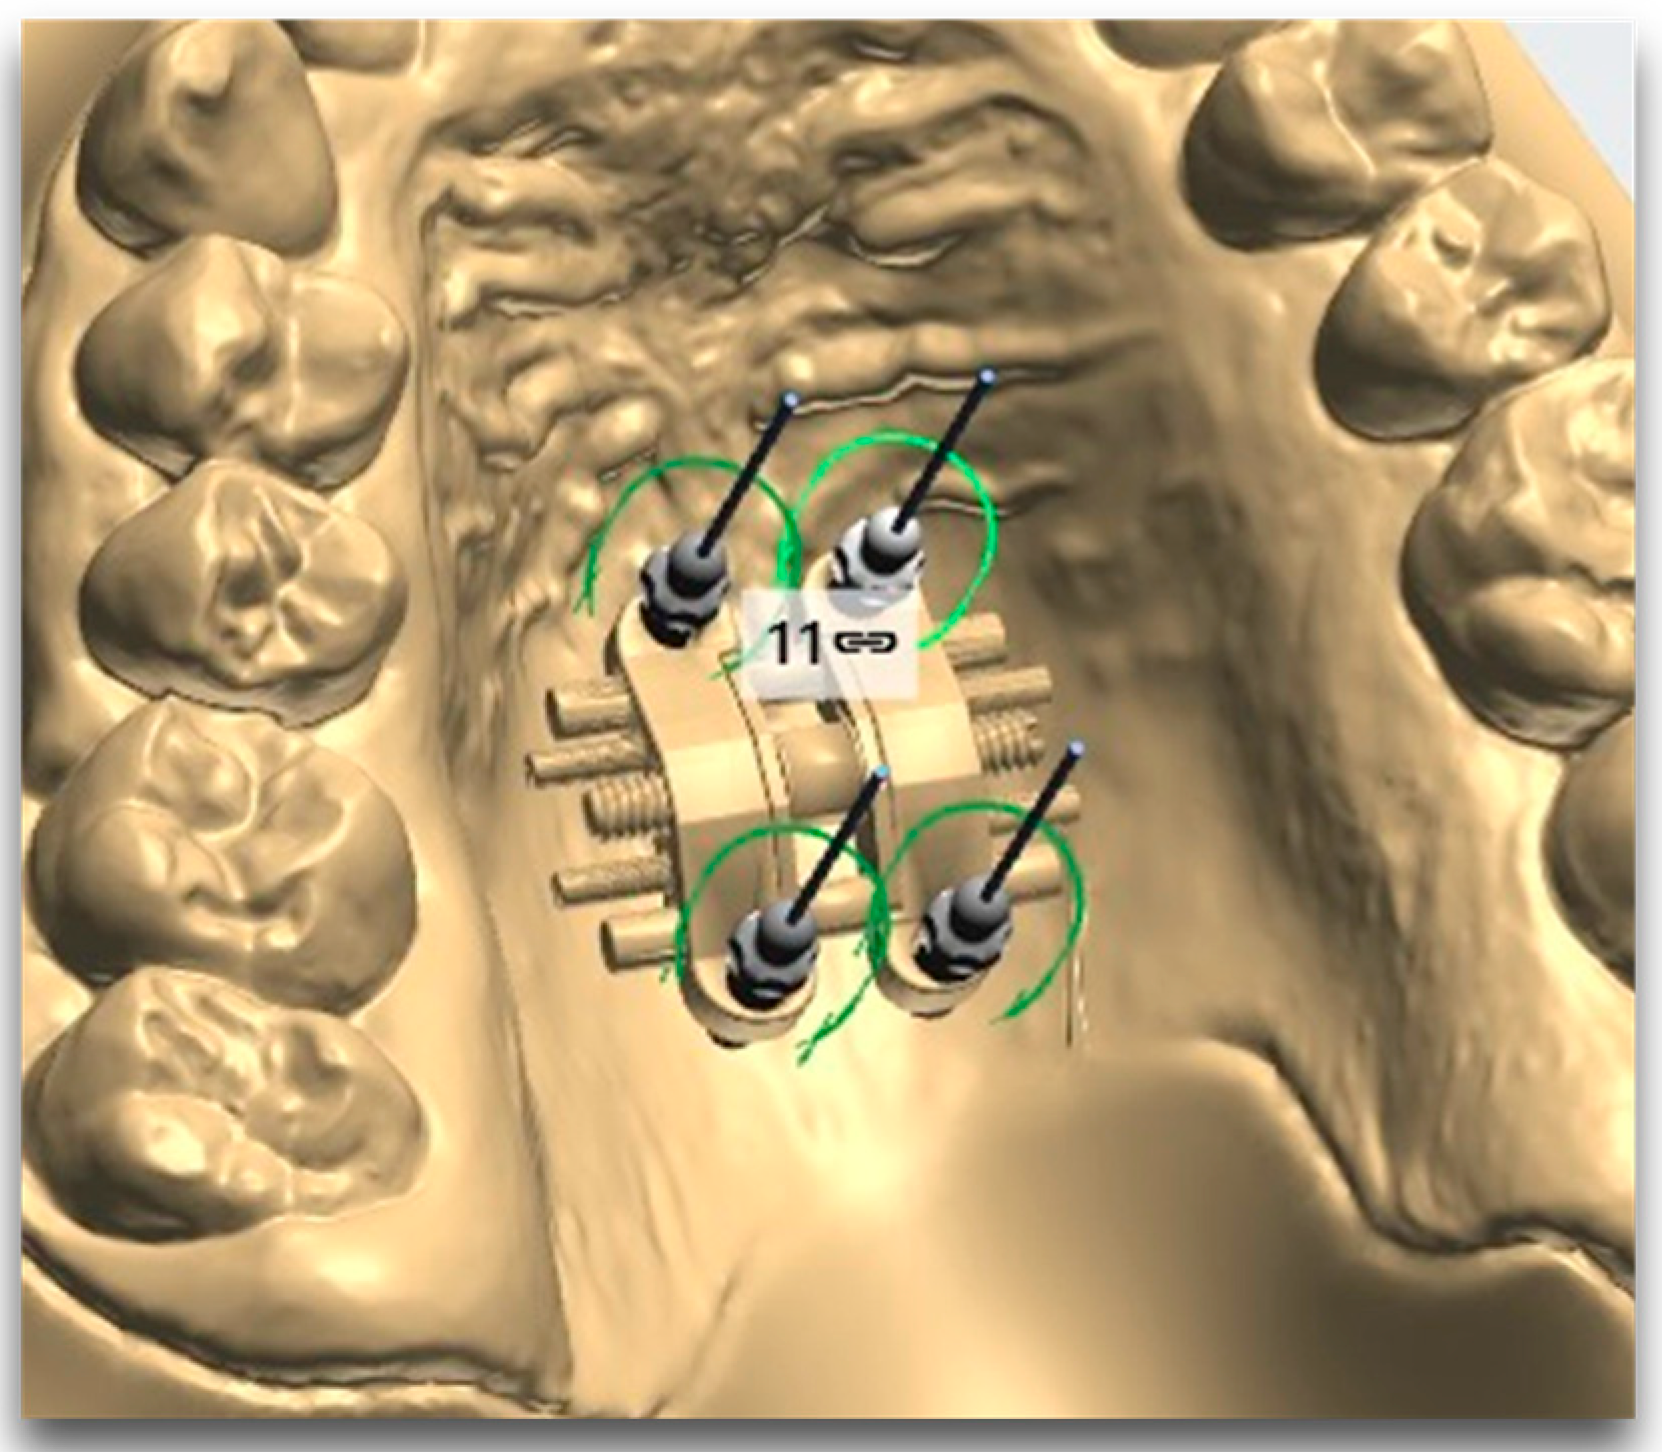

- The MSE system designed by Dr. Won Moon (Biomaterials Korea, Seoul, Republic of Korea) that has a jackscrew component with four parallel holes for mini-implant insertion and supporting arms on both sides soldered to the molar bands, aiming to stabilize the device’s position during expansion. Regularly, the position of the appliance is between the two zygomatic-maxillary buttresses, frequently located at the level of the first molars, so the mini screws are located just anteriorly to the soft palate [10,28]. An example of the posterior positioning of the MSE jackscrew with four mini-implants performed for a patient in our clinic, can be seen in Figure 2.